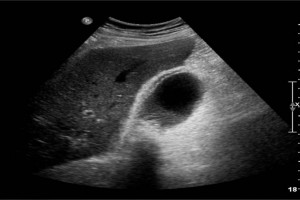

Diplomados en Ultrasonografía